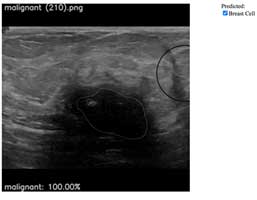

Breast cancer cell

(Ultrasound image)

- Highlight breast cancer location

- Classification with percentage